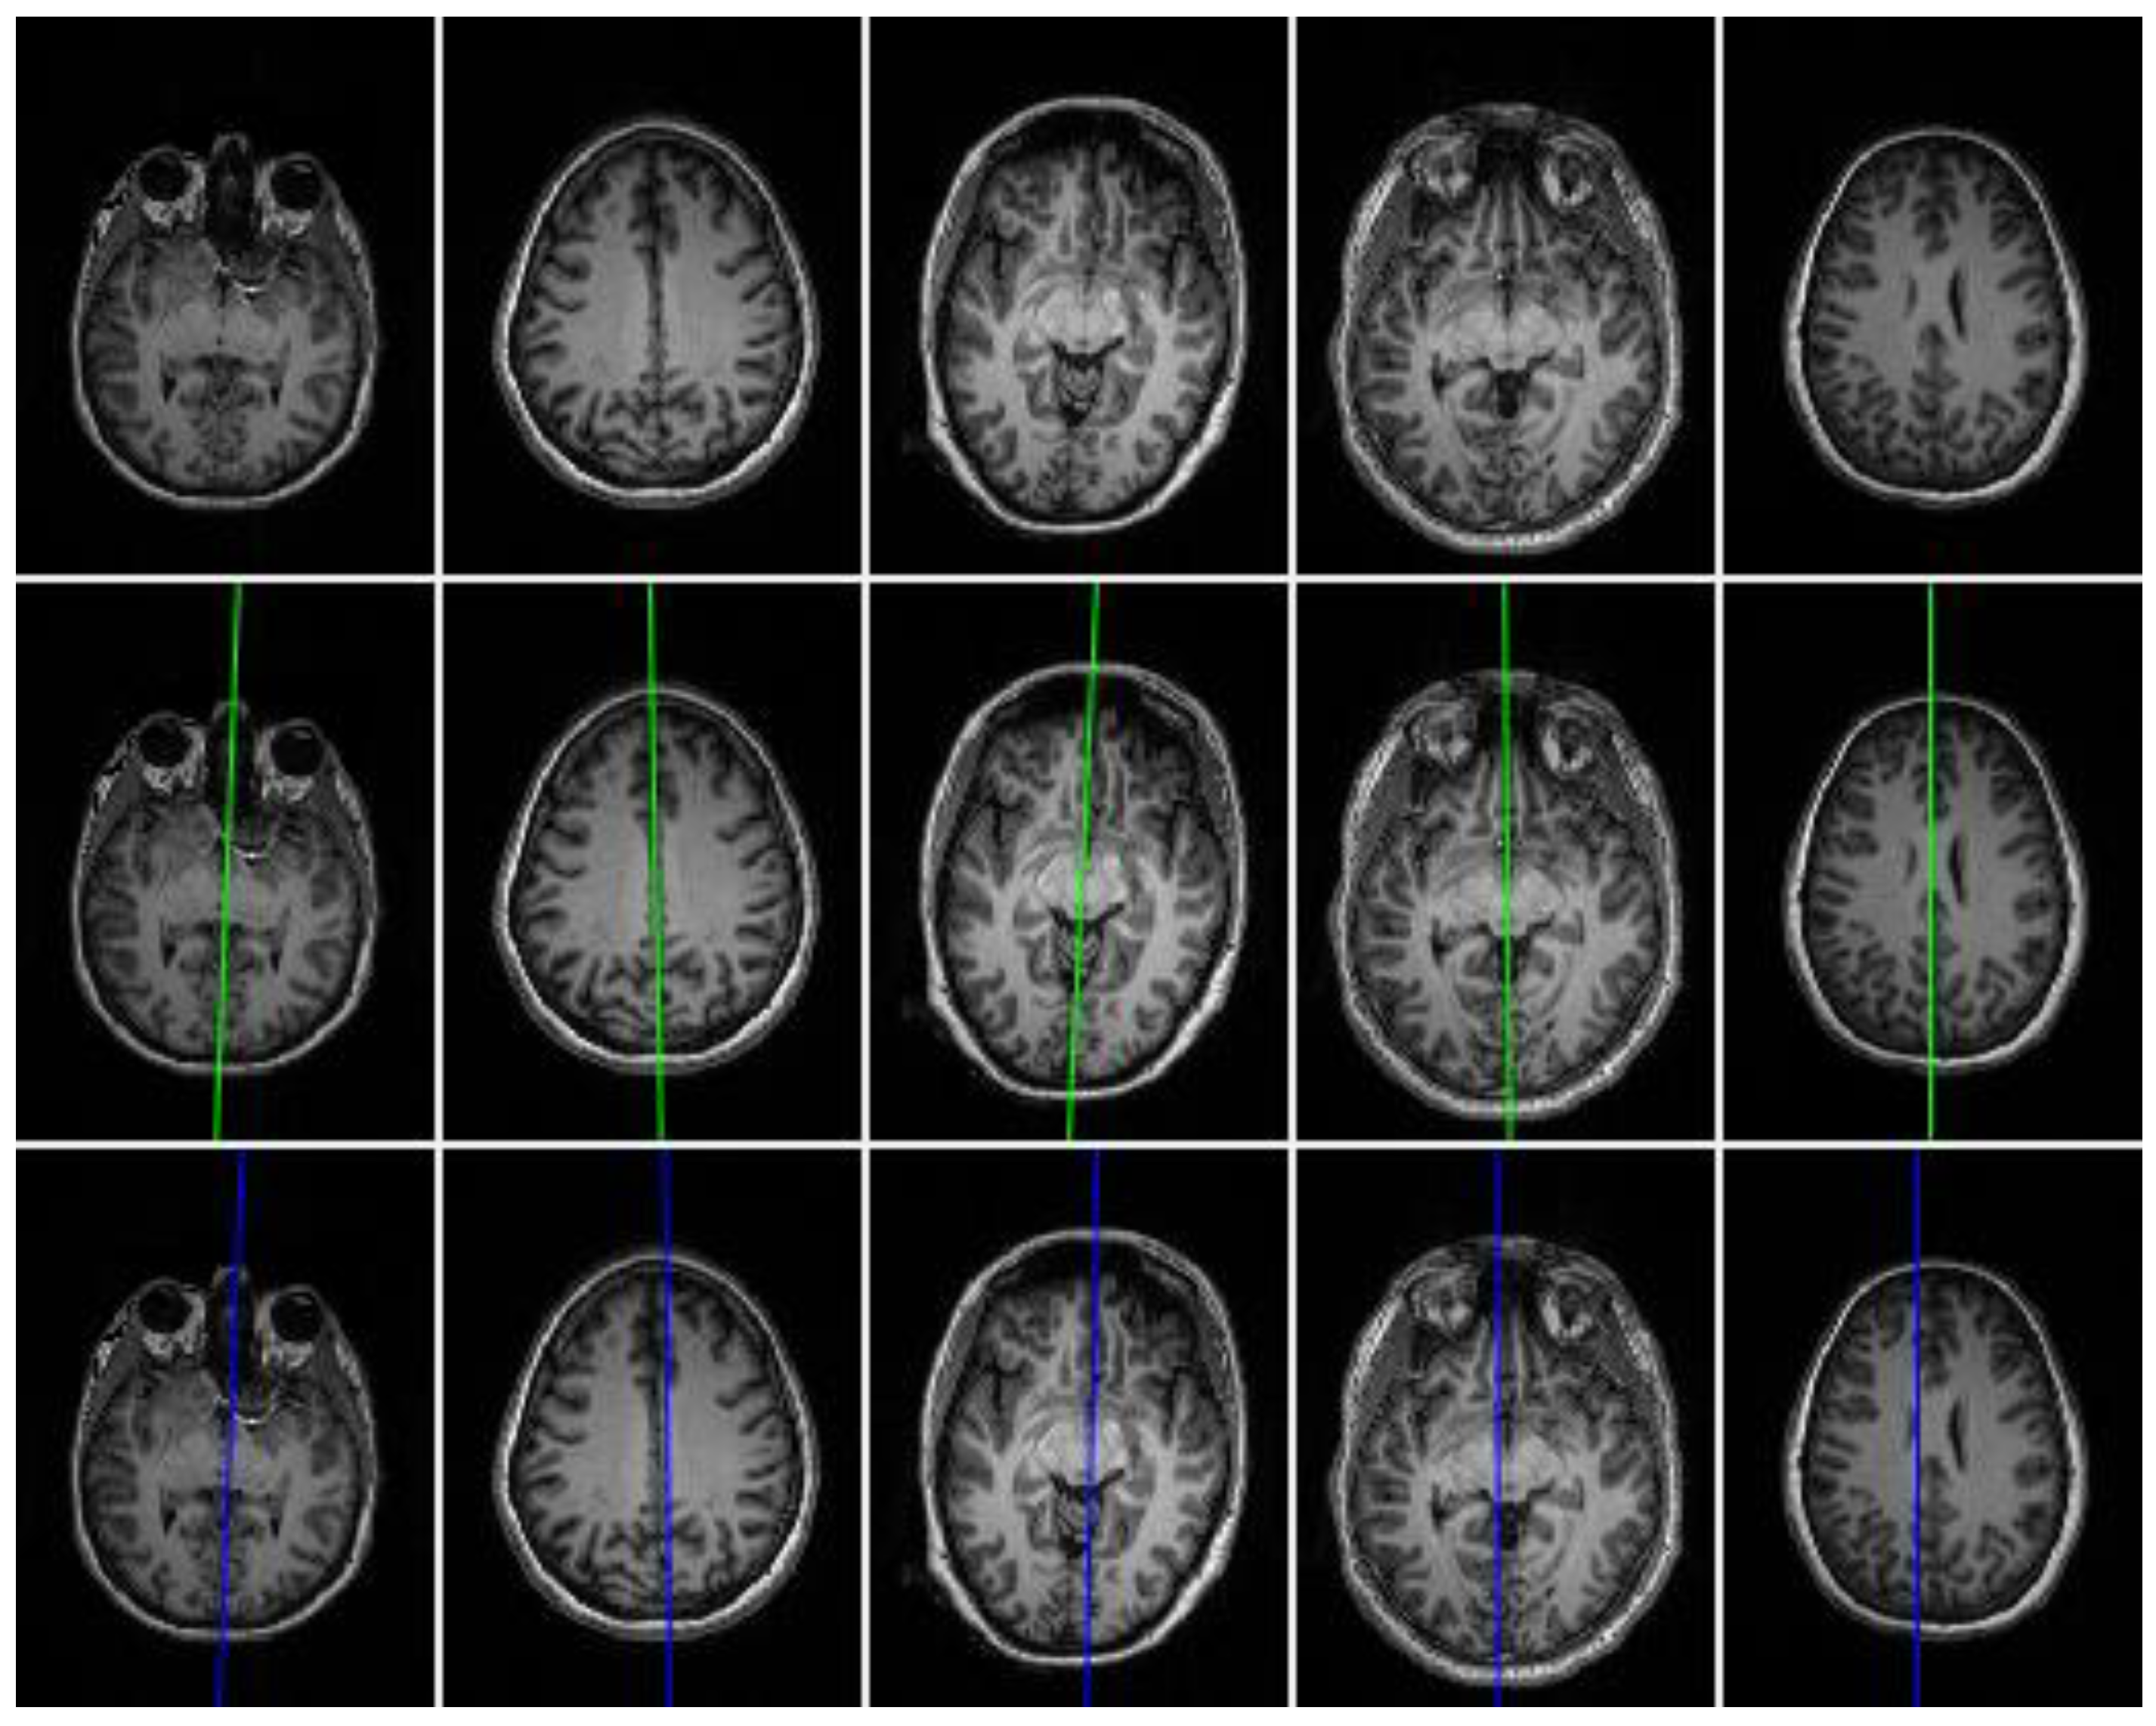

3. Results and Discussion

3.1. Evaluation on Real Datasets